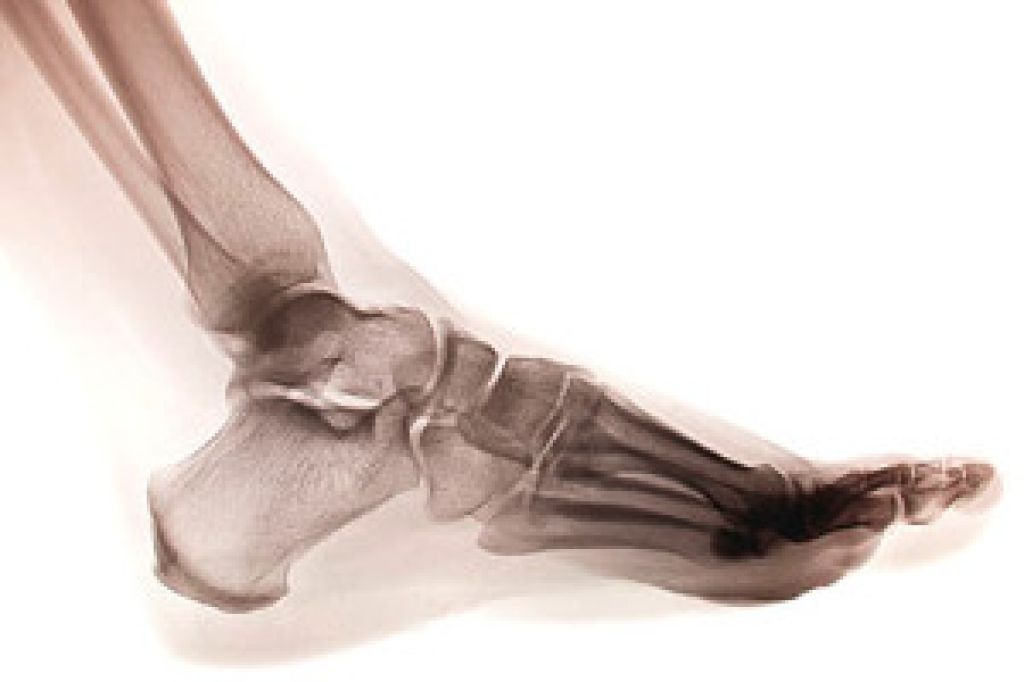

In order to diagnose your bunion, your podiatrist may ask about your medical history, symptoms, and general health. Your doctor might also order an x-ray to take a closer look at your feet. Nonsurgical treatment options include orthotics, padding, icing, changes in footwear, and medication. If nonsurgical treatments don’t alleviate your bunion pain, surgery may be necessary.